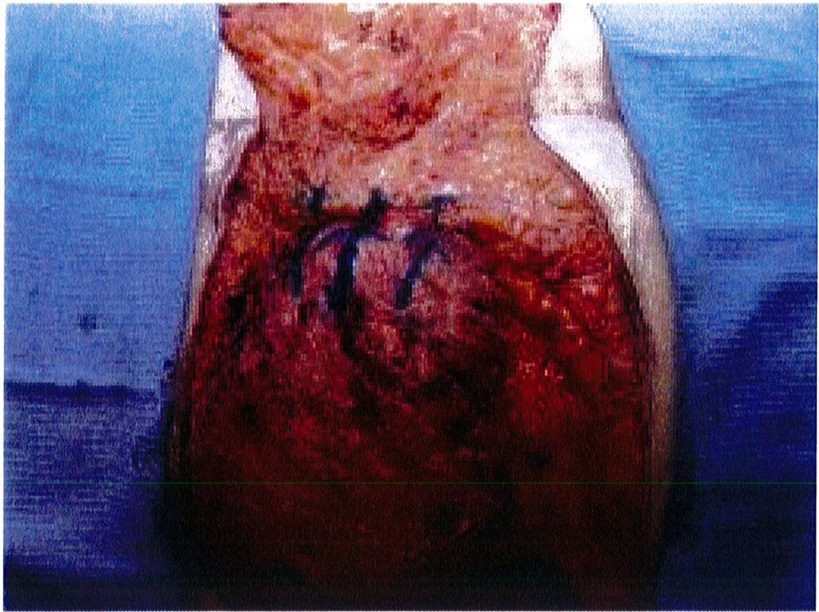

ở hình 5) được khử biểu mô bằng dao tay hoặc dao điện để bộc lộ tới phần cân nông. Phần ranh giới của mô trung tâm này được bóc tách tới lớp cân cơ, làm chúng bị cô lập với các tổ chức xung quanh. Sau đó sử dụng mũi purse-string khâu đính phần cân nông lại với nhau rồi thít chặt chỉ để hình thành nên một đảo chứa các tổ chức dưới da, cân cơ (Hình 6), đồng thời bảo tồn được toàn bộ mạch máu thần kinh phía bên dưới. Chúng ta có thể thấy kỹ thuật này không phá hủy mô quá nhiều, đồng thời có thế sử dụng chính tổ chức dưới da đế tạo ra điểm hình chiếu thẩm mỹ cho mông. Mũi khâu dây rút cũng rất hữu hiệu ở đây vì chúng giúp co các mối chỉ cùng nhau, từ đó dồn và đẩy mô trung tâm lên thành một khối hình cầu, như đang sử dụng một khối implant vậy!

Hình. 5. Khử biểu mô vạt mông. Ở vùng ranh giới tiến hành bóc tách sâu tới lớp cân sâu, bảo tồn các tổ chức mạch máu thần kinh. Da chỉ được khử lớp biểu mô để bảo tồn thể tích và tạo ra một mỏ neo vững chắc cho đường giữa.

Hình. 6. Đặt các mối khâu purse-string (như khâu túi dây rút) ở lớp cân nông. Mersilene 1 hoặc tương đương được sử dụng trong khâu này, chỉ khâu phải lướt dễ dàng qua các tổ chức.

Hình. 7. Chỉ khâu được đảm bảo thắt chặt với khoảng 6 nút thắt. Sau khi thít chỉ thì trông mô trung tâm sẽ nhô ra nhiều hơn, là cơ sở để tạo ra điểm hình chiếu sau này.